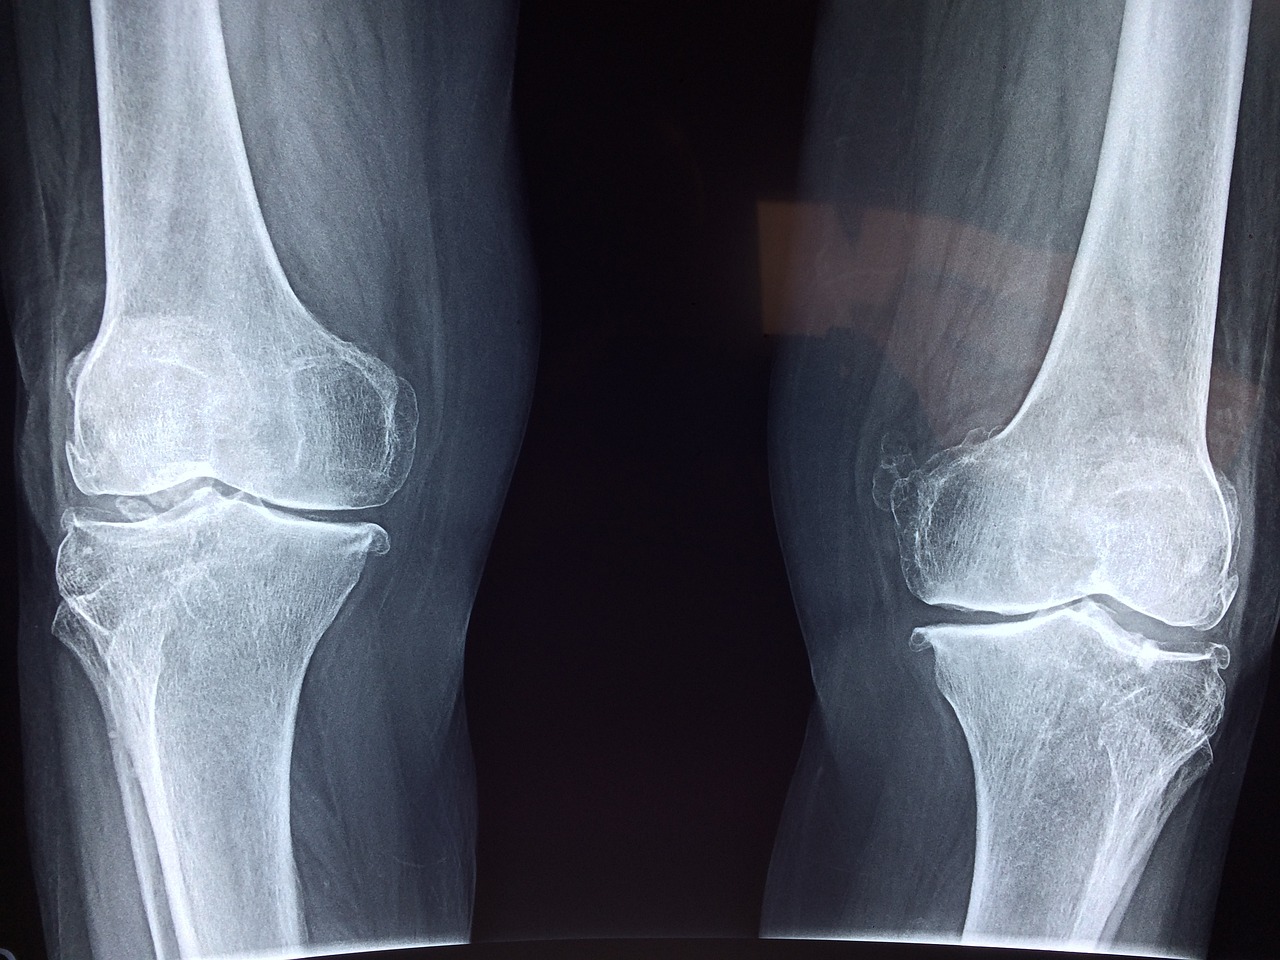

일반적으로 여러 관절에 지속적인 통증과 부종은 류마티스 관절염의 초기 증상의 특징입니다. 그리고 관절을 만지면 열감이 느껴지는 경우가 많습니다. 일반적으로 영향을 받는 관절에는 손, 손목, 무릎, 발이 포함됩니다.

9. 대칭적인 관절통증

류마티스 관절염은 일반적으로 신체 양쪽 관절에 대칭적으로 영향을 미칩니다. 한쪽 무릎이나 손이 영향을 받으면 반대쪽 동일한 부분의 관절에도 같은 증상이 나타날 수 있습니다. 이런 대칭적 증상은 류마티스 관절염을 다른 형태의 관절염과 구별하는 데 도움이 됩니다.